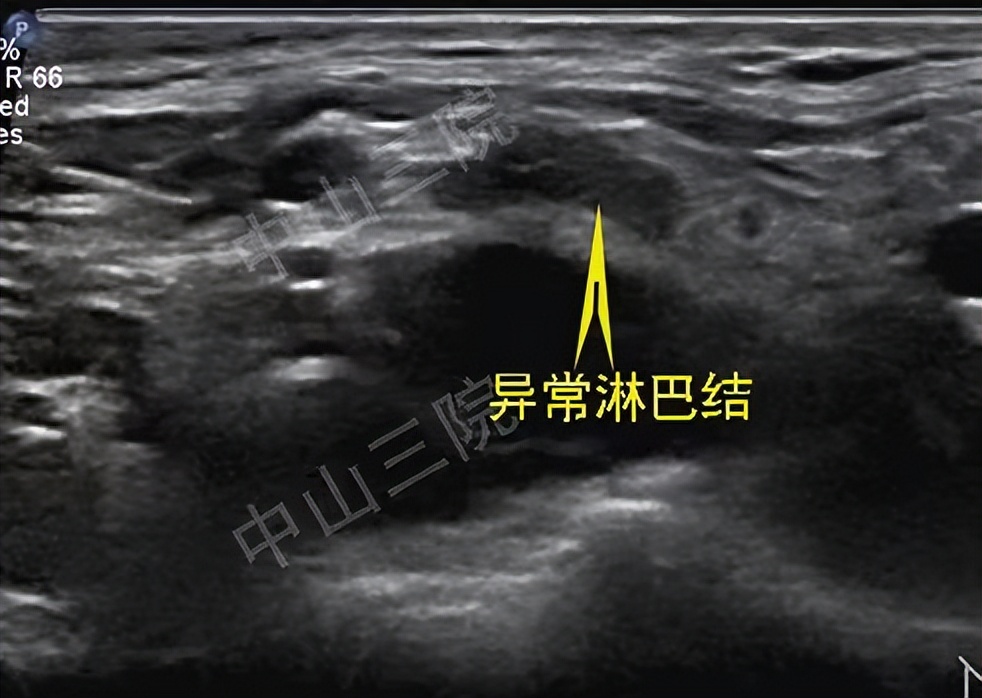

甲状腺癌热消融治疗无创、安全、简便,术后三年复查一切正常

她怀着试一试的心情找到了中山大学附属第三医院超声科的任杰教授,任教授先为欧女士做了详细的术前检查,结果显示只有右侧锁骨上窝的一枚淋巴结转移病灶,病灶局限,符合热消融治疗的适应证。皮肤上进行局麻后,欧女士清晰地感受到一根针穿入皮肤,不到一个小时,任教授说手术结束,她如此惊讶,没有明显的不适,没有剧痛,一切结束了!